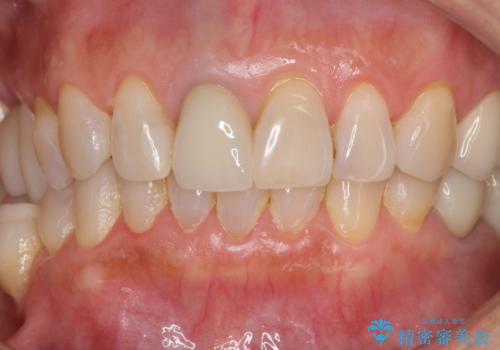

金属を全てセラミックに メタルフリー治療

上下奥歯の抜歯を同時期に行わず、下顎の治療を終えてから上顎を抜歯して治療を進めたため、1年ほどの期間を要しました。

口の中を一切気にしなくて良くなり、患者様には大変満足していただきました。